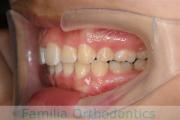

上の前歯が出ているのを治したいということで来院されました。上下のあごのズレが強く、上は小臼歯を、下は前歯を一本抜歯で対応しました。約2年半、30回程度の通院をしていただきました。前歯の移動量が大きく、歯根吸収のリスクが高いケースでした。

- ≫治療前